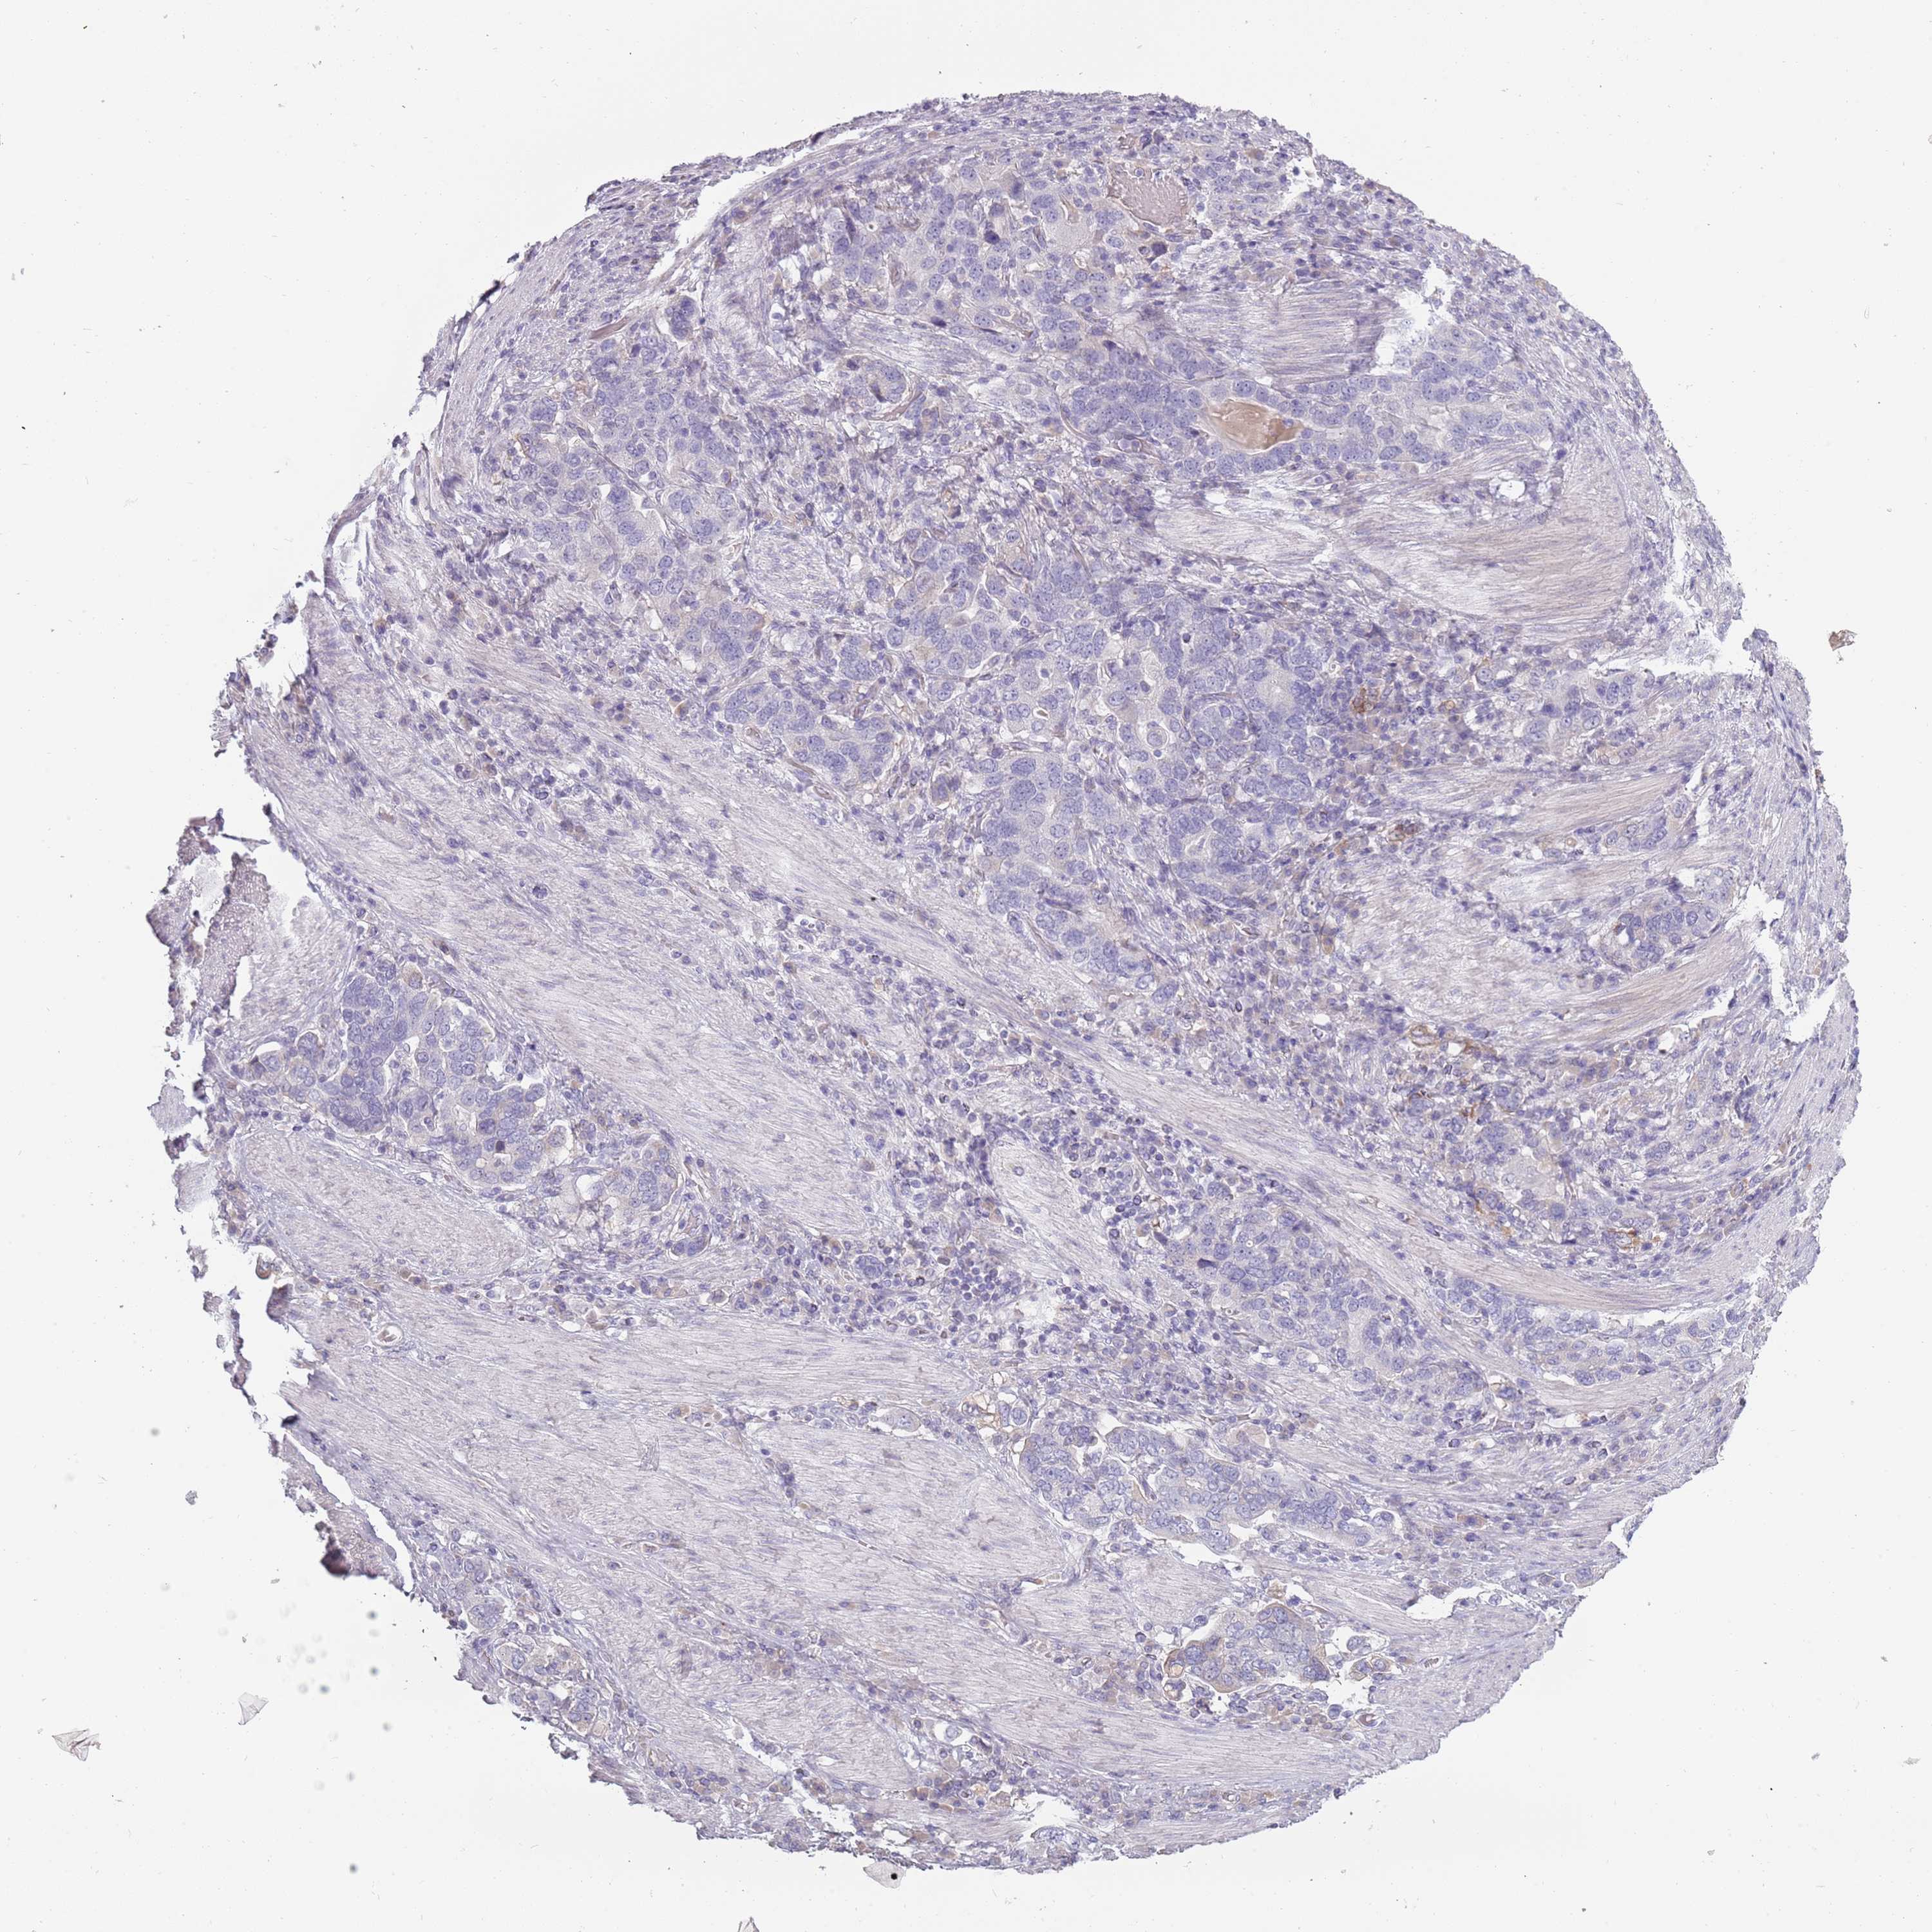

STOMACH CANCER - Protein expressioni

A mouse-over function shows sample information and annotation data. Click on an image to view it in a full screen mode. Samples can be filtered based on level of antibody staining by selecting one or several of the following categories: high, medium, low and not detected. The assay and annotation is described here.

Note that samples used for immunohistochemistry by the Human Protein Atlas do not correspond to samples in the TCGA dataset.

Antibody stainingi

Antibody staining in the annotated cell types in the current human tissue is reported as not detected, low, medium, or high, based on conventional immunohistochemistry profiling in selected tissues. This score is based on the combination of the staining intensity and fraction of stained cells.

Each image is clickable and will lead to virtual microscopy that enables deeper exploration of all samples and also displays staining intensity scores, fraction scores and subcellular localization as well as patient and tissue information for each sample.

Antibody HPA047154

Staining

High

Medium

Low

Not detected

Intensity

Strong

Moderate

Weak

Negative

Quantity

>75%

75%-25%

<25%

None

Location

Nuclear

Cytoplasmic/membranous

Cytoplasmic/membranous,nuclear

Adenocarcinoma, NOS